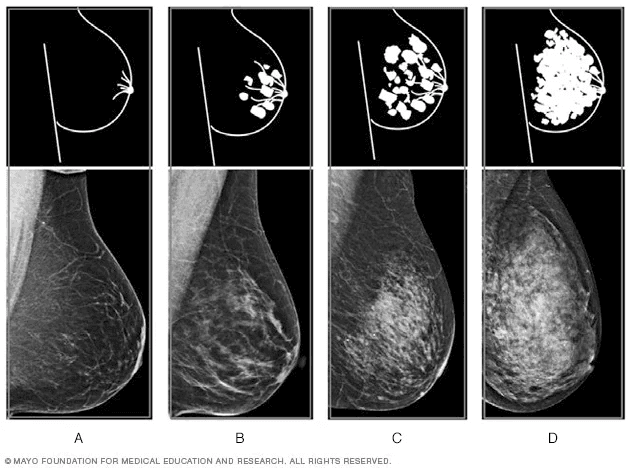

ঘন স্তন বলতে বোঝানো হয় স্তনের সেই অবস্থা যেখানে গ্রন্থি (Glandular) এবং ফাইব্রাস টিস্যু (Fibrous Tissue) বেশি থাকে, আর ফ্যাট কম থাকে। সাধারণত ম্যামোগ্রাম পরীক্ষায় এটি ধরা পড়ে।

স্তনের ঘনত্ব চোখে দেখে বোঝা সম্ভব নয়। শুধুমাত্র ম্যামোগ্রাম বা ব্রেস্ট ইমেজিং পরীক্ষার মাধ্যমেই তা নিশ্চিত করা যায়। তবে কিছু সাধারণ বৈশিষ্ট্য রয়েছে:

📌 চিকিৎসকরা সাধারণত BI-RADS স্কোর দিয়ে স্তনের ঘনত্ব নির্ণয় করেন।